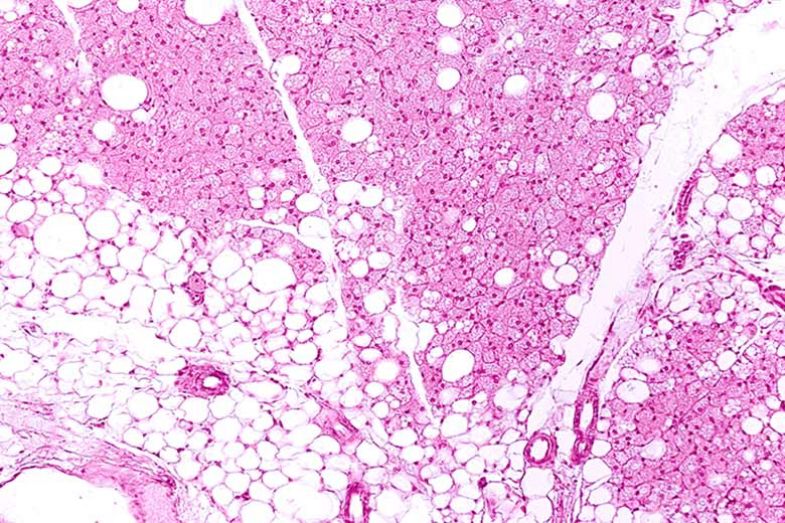

Adipose tissue: body fat storage

Under healthy conditions, body fat is stored as adipose tissue, accumulated in regions such as the abdominal area, back, legs, and face. 80 to 90% of this tissue is composed of adipocytes, cells that are highly specialized in fat storage. Depending on their morphological and biochemical characteristics, they can be distinguished into three specific subtypes: white, beige, and brown (Hadi et al., 2019; González Jiménez, 2013; Mayoral et al., 2020). Their main function includes reserving fat for energy and producing molecules that regulate other functions such as hunger and the immune system.

Under unhealthy conditions such as obesity, adipose tissue fails to function correctly and disruptions in adipocytes occur, such as increased size, increased inflammation, and decreased sensitivity to the hormone that regulates blood glucose levels (insulin). All these changes suggest that adipose tissue is the ideal target for innovative treatments to combat obesity.